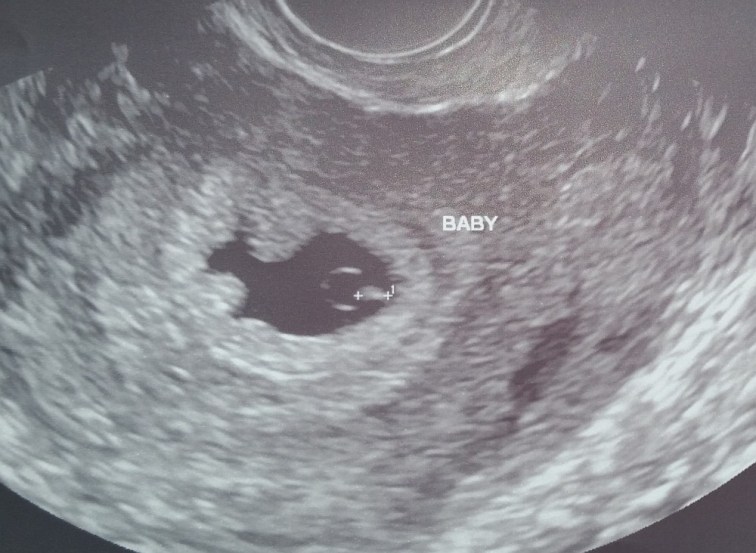

With baby B on the way, I find myself trying to get excited, but I’m having a difficult time. I think I’m trying to keep my distance, not think about the baby much in hopes that if things go wrong, I’ll feel less broken than I did when we lost Lily.

I don’t want to be cold and distant about the potential of being a father, but with two losses now behind me, I can’t fathom a third. I keep telling Annie and others that I’ll breath easier once we get to Halloween. At that point, Bea should be far enough along that, despite being super early, he or she can survive thanks to medical science.

The idea of trying to remain emotionally distant from the baby my wife is growing over the next seventeen or so weeks seems a little crazy to my more rational side.